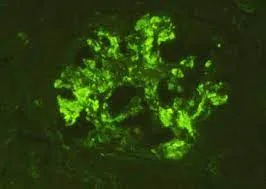

Injúria Renal Aguda (revisão Lancet 2025)

Injúria Renal Aguda (revisão Lancet 2025)